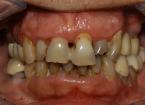

Riabilitazione completa superiore e settori posteriori inferiori

Paziente F, 52 anni, riabilitazione implanto-protesica completa superiore, ad appoggio dentale ed implantare. Riabilitazione implanto-protesica dei settori postero-laterali inferiori su denti naturali e su impianti.